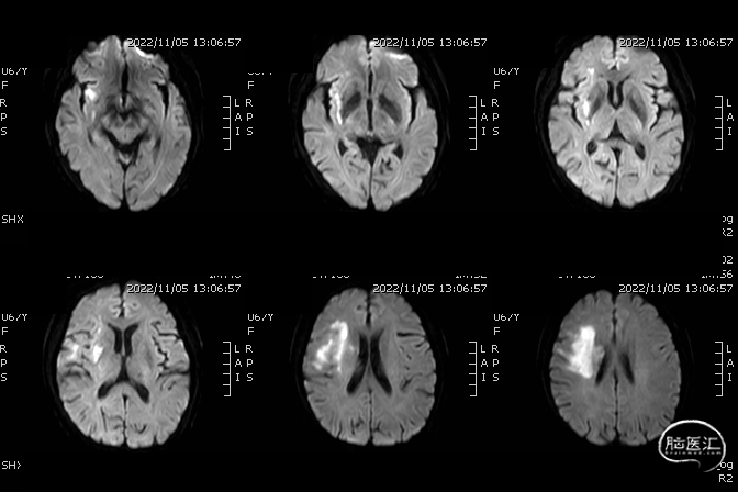

术前影像检查

MRA:右侧大脑中动脉闭塞。

DWI:右侧额顶叶、岛叶、基底节区新鲜梗死病灶。

脑血管造影:3型主动脉弓,右侧颈内动脉起始段闭塞,后循环及左侧颈内动脉均未向左侧颈内动脉供血区代偿。